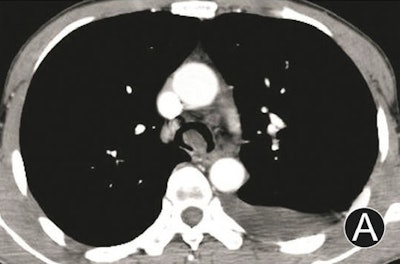

- Intraluminal and extraluminal tumors: These manifest as infiltrated growth along thickened walls, with invasion extraluminally, and masses both intraluminally and extraluminally.

Tumors with dominant intraluminal growth have significant luminal stenoses, the group noted. Tumors with evident extraluminal growth may resemble mediastinum tumors. Tumors with apparent intraluminal and extraluminal growth have large masses and are often obstructive.

Each advanced reconstruction technique has unique advantages. MPR was used to obtain 2D multiplanar images centering on the trachea; it can reflect different tissue densities by using different attenuation scales with high-density resolution and no obvious artifacts, Luo and colleagues wrote.

The results demonstrated that MPR could not only display the locations, morphologies, internal features, and extramural invasions of primary trachea and main bronchus tumors, along with morphologies and extents of luminal stenoses, it could also measure their longitudinal involvement and distances between main bronchus tumors and trachea carinae. However, due to the 2D images, MPR could not provide a 3D effect, according to the researchers.